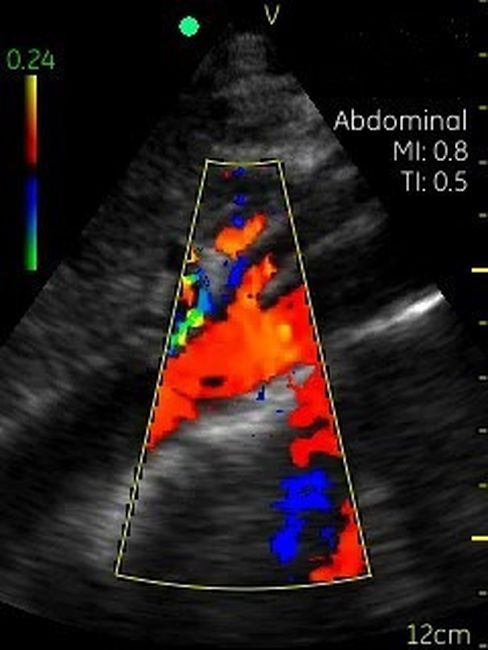

Невозможно было представить раньше, что УЗИ аппарат может помещаться на ладони руки человека. Теперь это реальность, воплощенная в корпусе и технологической начинке GE VSCAN. Инженеры заложили возможность получения дополнительной визуализации кровотока с цветной кодировкой в режиме реального времени для полноценной постановки диагноза на месте.

Визуализация Vscan:

· Черно-белый режим для визуализации анатомических структур в реальном времени.

· Наложение кровотока с цветовой кодировкой в реальном времени.

· Поле зрения в черно-белом режиме: до 75 градусов с максимальной глубиной 25 см.

· Сектор цветного режима показывает кровоток с углом обзора 30 градусов

· Широкополосный фазированный датчик с частотой от 1,7 до 3,8 МГц.